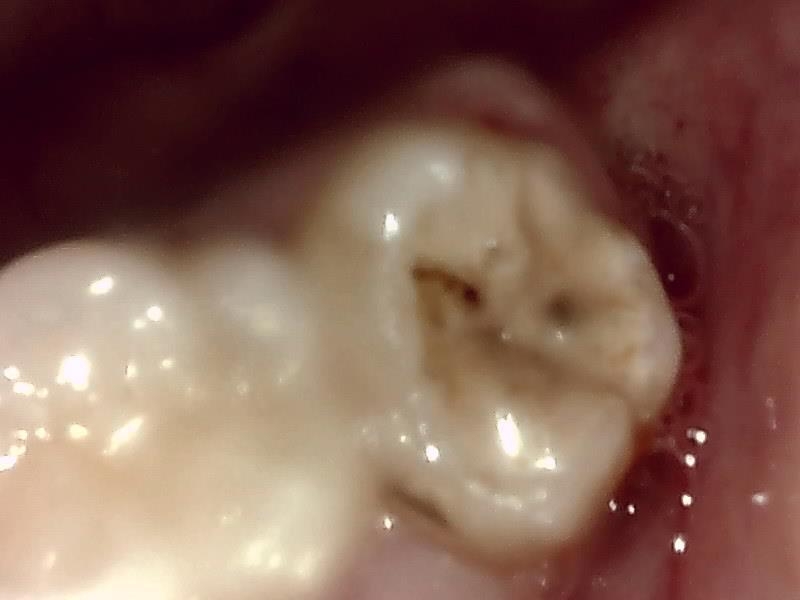

歯牙分割

当院では、傷口は最小限に、骨は極力削らずに行います。

骨が歯を覆っているケース以外は骨を削ることはありません。

親知らずのみにアプローチし歯を分割し最小限の傷口で取り出します。